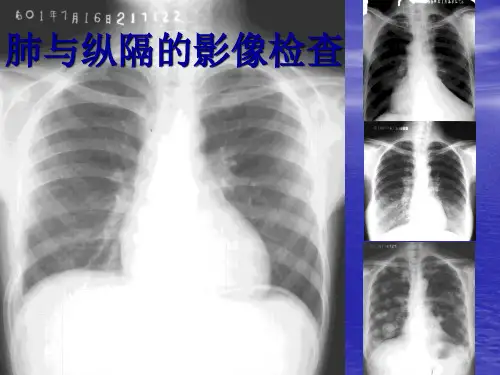

升主动脉 上腔静脉 右肺动脉